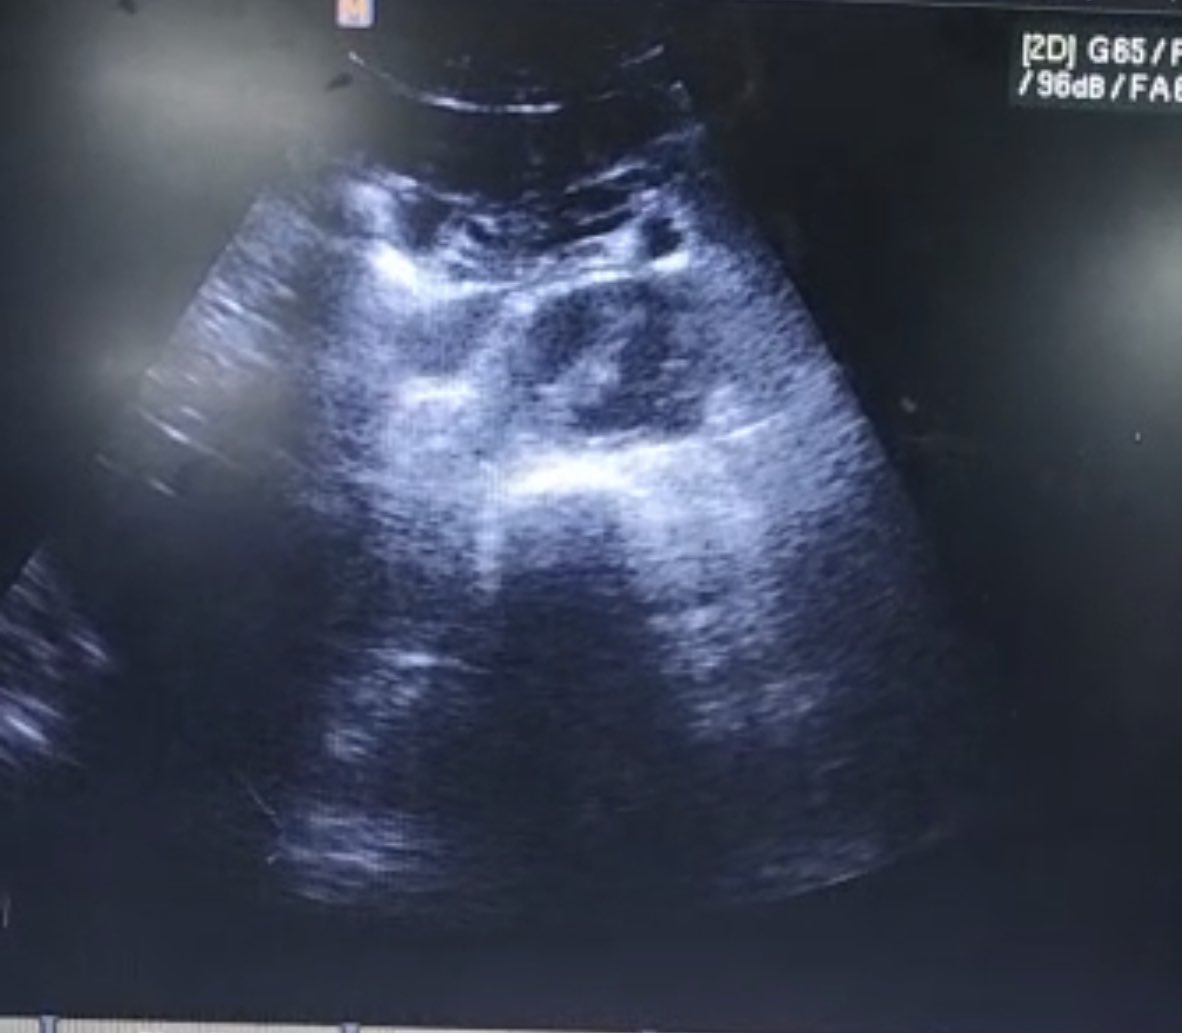

Mujer de 60 a. Ant : DM . Acude con dolor abdominal , fiebre y signos de hipoperfusión . ( I ) ( II / zoom ) Imagen anecogénica de bordes irregulares dentro de parenquima hepático : Absceso hepático #Pocusfirst #EM #PAUSE